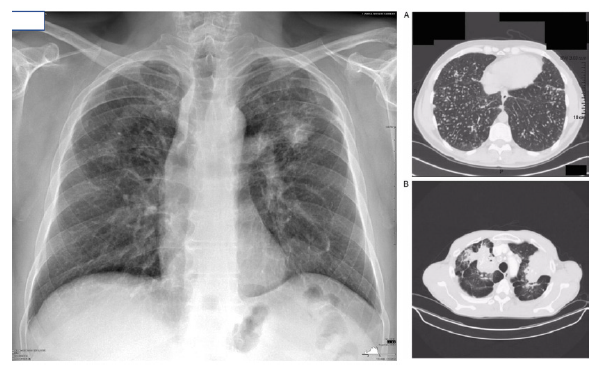

Silicosis avanzada: En esta etapa avanzada de la enfermedad, las opacidades redondas se extienden por todo el pulmón (lo cual es menos común) o se agrupan formando masas mayores a 1 cm de diámetro. El espectro radiográfico es amplio y complejo. La retracción pulmonar conduce a la formación de enfisema compensatorio o bullas, lo que hace que las infecciones del tejido pulmonar sean poco visibles. La alteración funcional puede variar desde ninguna hasta disnea en reposo. La afectación del ventrículo derecho del corazón dependerá del grado de destrucción del lecho vascular pulmonar y del nivel de hipoxemia que presente el paciente, lo que puede llevar desde ninguna repercusión hasta insuficiencia cardíaca derecha. La respuesta inmune en estos pacientes puede estar gravemente comprometida, lo que los hace muy susceptibles a las infecciones respiratorias bajas. Desde el punto de vista legal, esta forma de silicosis generalmente se califica con una pensión parcial (50% de incapacidad según Compín) y rara vez se concede una pensión completa (80% de incapacidad según Compín). Ver imagen 3.

Imagen 3 Diferencia entre radiografía de tórax con técnica OIT y Tomografía computadorizada de tórax de alta resolución (TCAR), en la imagen A opacidades redondas confluyentes típicas de silicosis y en la imagen B coalescencia de opacidades redondas con formación de silicomas que puede caracterizar una fibrosis pulmonar masiva en curso. Imágenes gentiliza de reproducción del Dr. Anselmo López Guillén y Dr. Sergio Rovira Sans.